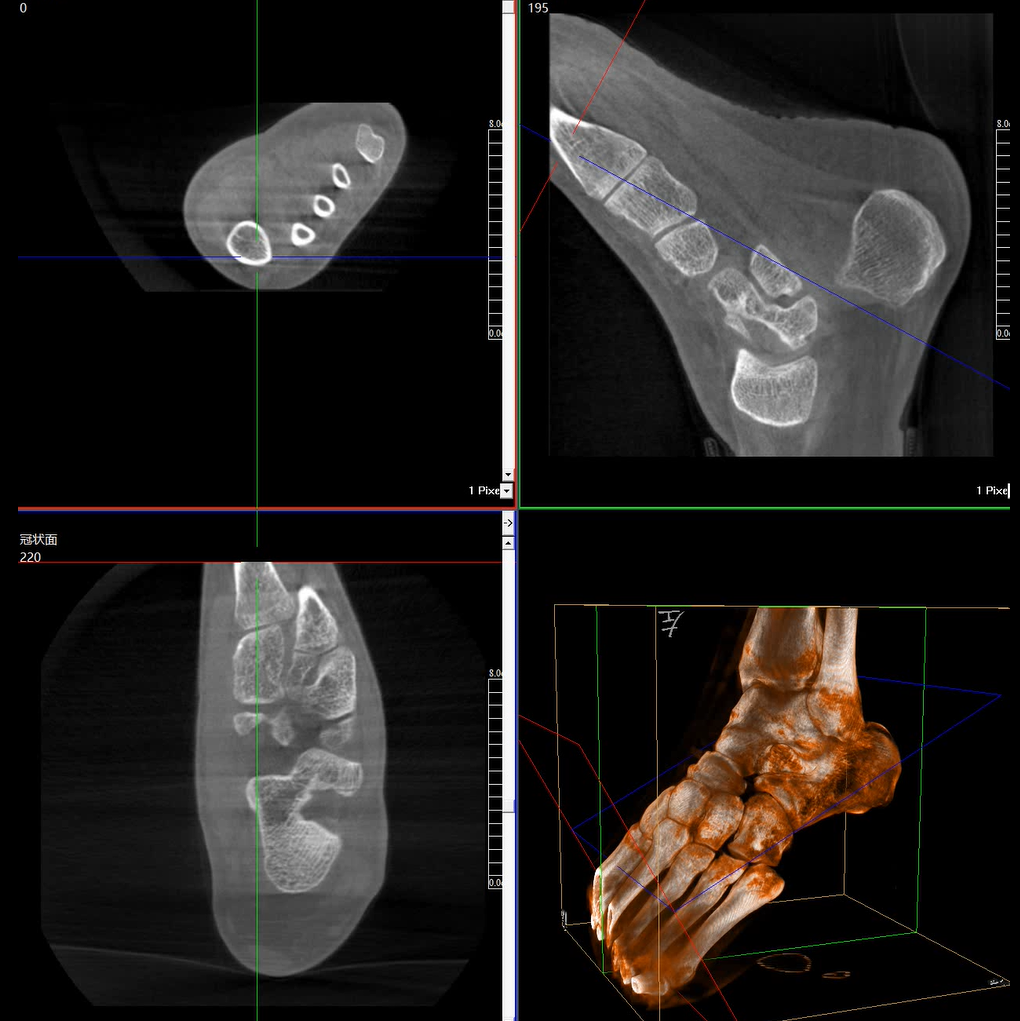

術(shù)中三維成像和橫斷面圖像提供多角度的手術(shù)診斷信息,輔助醫(yī)生進行術(shù)中評估判斷,諸如骨折復位情況和內(nèi)植入螺釘?shù)某叽绾臀恢茫o助手術(shù)更好地完成。

提供更大的術(shù)中三維成像視野,采集更多圖像信息,可一次拍全全段頸椎、全段腰椎、七節(jié)胸椎、雙側(cè)骶髂關(guān)節(jié)、股骨頭及單側(cè)盆骨。